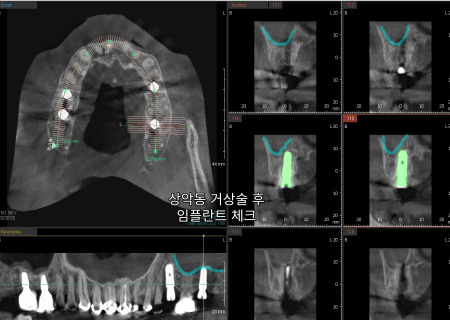

3D CT와 구강 스캔을 통해

사진처럼 3차원의

해부학적 구조를

관찰하는 모습입니다.

특히 위턱의 경우

입천장 부근에 있는

얇은 상악동 막이 존재해

다치지 않도록

심는 위치와 뼈상태를

정밀하게 살펴야 합니다.

상악동 거상술을 통해

주변의 구조물이

다치지 않도록 했습니다.